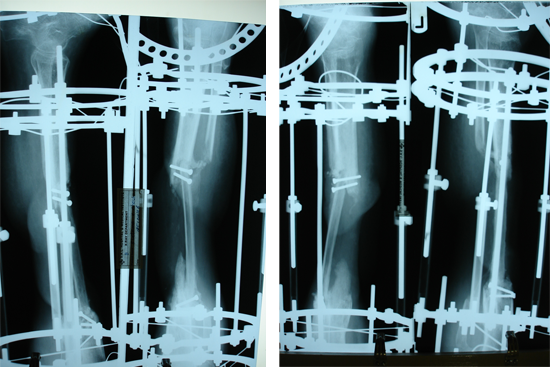

Tibialisation Of Fibula

Shankar Giri

Sudama

Wagh